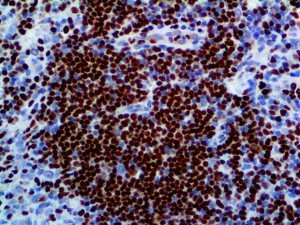

It is the ICU physician who is most likely to witness one of the deadliest manifestations of the abnormal immunological response, the cytokine storm syndrome (CSS). This response is also referred to by some as the cytokine release syndrome (CRS). CSS is characterized by continuous activation and expansion of macrophage and lymphocyte populations, which secrete large amounts of cytokines, causing the cytokine storm. This massive cytokine release is akin to hemophagocytic lymphohistiocytosis (HLH) disease, a syndrome characterized by initial unchecked and persistent activation of cytotoxic T lymphocytes and NK cells.

Clinical and laboratory manifestations of HLH include fever, enlarged liver and/or spleen, neurologic dysfunction, coagulopathy, liver dysfunction, cytopenias (i.e., low levels of erythrocytes, leukocytes, and/or platelets), hypertriglyceridemia, hyperferritinemia, hemophagocytosis, and eventually diminished NK cell activity as the immune system becomes progressively paralyzed. HLH can be familial (primary HLH) or secondary to another disease process (sHLH), such as rheumatic disease, in which it is referred to as macrophage activation syndrome (MAS, characterized by elevated ferritin).